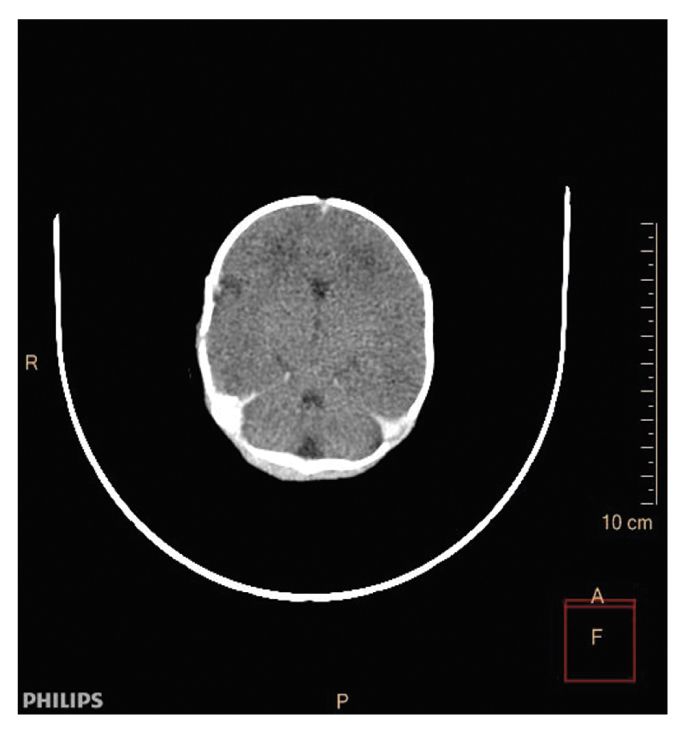

При исследовании трупа с помощью метода КТ врачом-рентгенологом выявлены диффузные изменения плотности вещества мозга — вероятно, сочетание гипоксических и посмертных изменений. Данных за интракраниальную гематому не получено. Дополнительная полость 5-го желудочка — вариантная анатомия (рис. 2). Содержимое в носоглотке. Небольшое количество содержимого в полости рото- и гортаноглотки с сохранением их просветов. Признаки кардиомегалии. Признаки гинекомастии. Диффузная гиперплазия обоих надпочечников. Вывих левой плечевой кости (рис. 3). Расправление легких. Наличие воздуха в петле тощей кишки и нижнеампулярном отделе прямой кишки (рис. 4). Жидкостное содержимое в желудочно-кишечном тракте с равномерным распределением (рис. 5). Наличие ядер окостенения в грудине (рис. 6). Наружный нос и ушные раковины сформированы правильно.

Рис. 2. КТ головного мозга: дополнительная полость 5-го желудочка — вариантная анатомия.

Fig. 2. Computed tomography scan of the brain: The 5th ventricular cavity — variant anatomy.